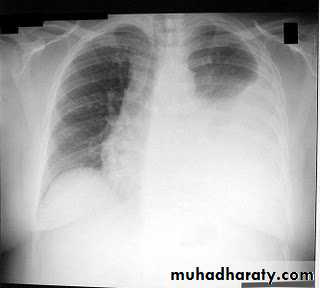

The classical appearance of pleural fluid on the erect PA chest film is homogenous opacity starting from the lung base with blunting the costophrenic angle and ascending towards the axilla (meniscus sign).

Previous scarring or adhesions in the pleural space can cause localised effusions

Chest x ray erect position, P-A view: blunting of the costophrenic angle on the right side, occurs once 200 ml of pleural fluid has accumulated.

A homogenous opacification is noted in the right lower zone with the opacity seen to track along the lateral chest wall. The right costophrenic angle is obliterated with a meniscus noted. Findings of a right sided pleural effusion.